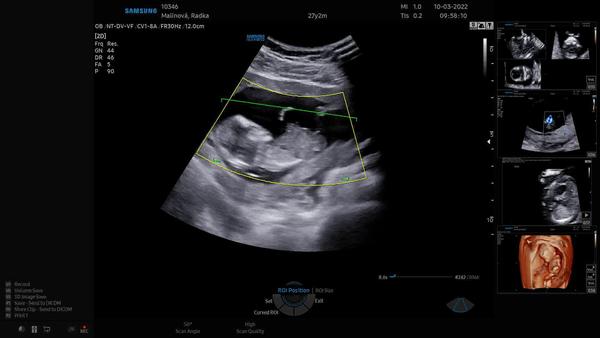

včera jsme byli na 1. screeningu a na pracovišti, kde jsme byli, říkají pohlaví až od 16. tt. Jsme objednaní na izo období na ultrazvuk, ale vím, že jinde říkají pohlaví i dříve. Nevíte, prosím, dle fotek, co čekáme?

Gestační věk miminka je 13+4.